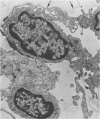

With removal of large numbers of macrophages by airway lavage, Type 1 cells were isolated in heterogeneous cell populations following the stepwise dissociation of lung tissue. Using a carefully timed collagenase-trypsin digestive sequence at 37 C, unwanted cellular and noncellular lung components were minimized prior to selective release of Type 1 cells. Resulting heterogeneous cell suspensions containing well-preserved Type 1 cells, as determined by electron microscopy, were layered onto a shallow gradient (3 to 6% Ficoll in minimal essential medium [MEM]) and separated at unit gravity into enriched subpopulations of various cell types. These included various fractions enriched with respect to Type 1 cells (70%), Type 2 cells (82%), and macrophages (81%). Identification of Type 1 cells following their isolation and gradient enrichment was established by light microscopic staining techniques and by specific cell surface characteristics in vitro as visualized by electron microscopy.